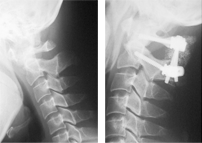

경추골절 및 탈구

경추골절 및 탈구 수술 전/후 X-ray

수술 전

수술 후